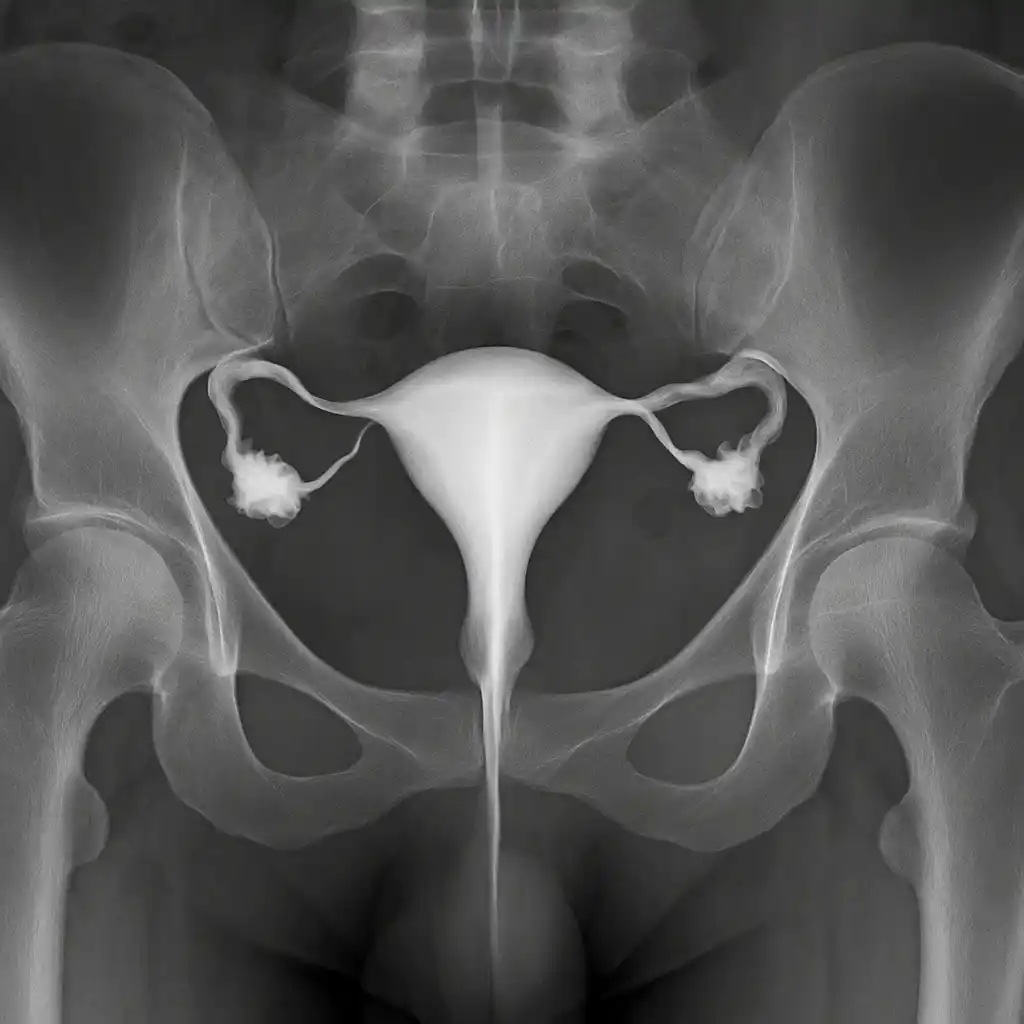

تعرضت الفنانة زينة لإصابة خلال تصوير أحد المشاهد، حيث شعرت بألم مفاجئ في الركبة، وبعد الفحص بالأشعة تبين وجود شرخ في الرضفة (كسر في عظمة رأس الركبة).

يحدث شرخ الركبة الذي يسمى بكسر الرضفة (بالإنجليزية: Patellar Fracture) طبيًا عادةً نتيجة صدمة مباشرة على مقدمة الركبة، مثل السقوط أثناء المشي أو الرياضة، أو التعرض لضربة قوية أثناء الحوادث المرورية أو الأنشطة اليومية. كما يمكن أن ينشأ نتيجة الإجهاد المتكرر على الركبة عند بعض الرياضيين، أو ضعف العظام الناتج عن هشاشة العظام أو الأمراض المزمنة، مما يجعل العظمة أكثر عرضة للكسر حتى مع إصابة بسيطة. حدثت إصابة زينة بشرخ في الرطبة نتيجة سقوطها في موقع التصوير.